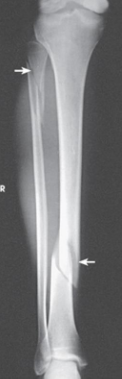

What projection is this

AP Projection leg

What projection of the leg is this

lateral leg projection

Patient position for lower leg AP projection is

supine

For an AP projection of the leg, femoral condyles are ____ to IR

parallel

CR enters the ____ for an AP leg projection

center of leg

Proximal and distal articulations of tibia and fibula moderately overlapped are seen in a

AP leg projection

What type of lateral is a lateral leg projection

mediolateral

Patient position for a lateral (mediolateral) leg projection is

supine, rotated towards affected side

In a lateral leg projection, femoral condyles are ____ and ___ to IR

superimposed, perpendicular

For a lateral leg projection, the CR enters at

midpoint of leg

Distal fibula superimposed by posterior half of

the tibia

• Slight overlap between tibia and fibular head

• Separation of the tibial and fibular bodies (not at

ends)

seen on a